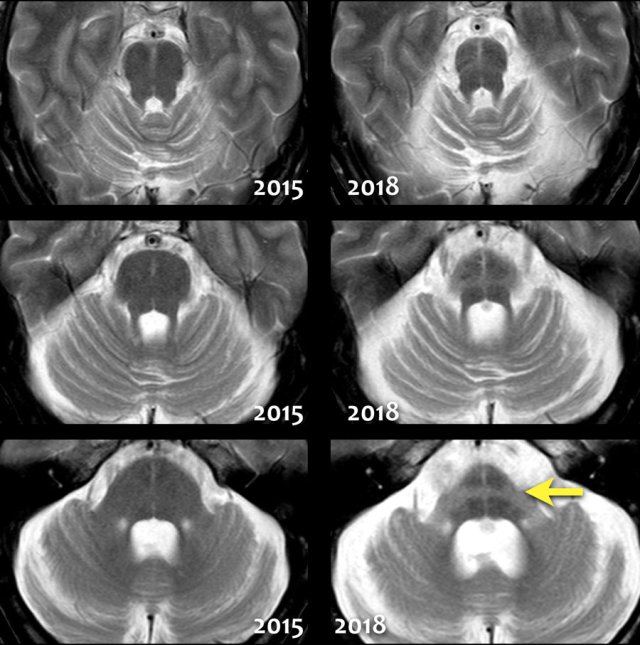

In MSA there is pronounced cerebellar atrophy and severe atrophy of the pons.

In MSA-P: low T2 SI dorsolateral putamen and slit-like increased SI lateral to putamen on T2.

In contrast to PSP, we don't see the humming bird sign, because the midbrain has a normal convex upper border.

The so-called 'hot cross bun sign', which is a result of pontine hyperintensity, is typical for MSA-C.

Notice the extreme atrophy of the pons and the cerebellum in this patient when we compare images of 2015 with images of 2018.